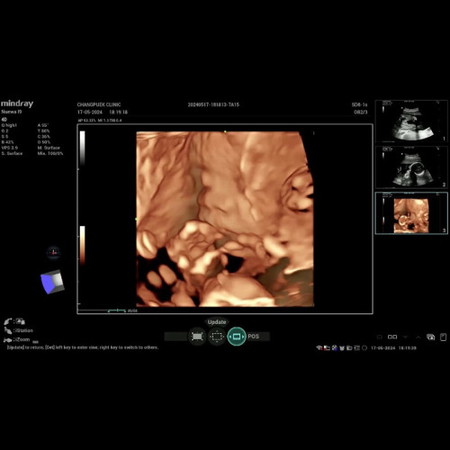

อัตราซาวด์ 4 มิติ

ที่คางลูกสายสะดือหรือมือคะ ดูไม่ออกเลย😂

เราอัตราซาว4มิติ น้องกอดสายสะดือเลยค่ะ กว่าหมอจะได้ภาพเขาไม่ยอมให้สแกน555

มือคะ